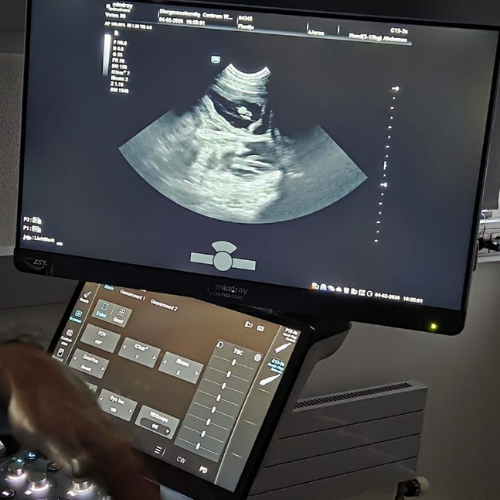

Vandaag heeft Fientje haar echo gehad.

Ik ben zo ontzettend blij, Fientje is drachtig!

Op de echo zijn meerdere pups te zien.

Ongeveer 8 maart 2026 is Fientje uitgerekend.